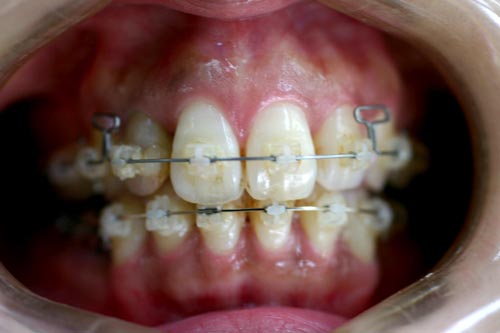

上顎の中央の歯一本が前にとびだしている治療例

Before

上顎の中央の歯一本が前にとびだしている症例です。これだけ前に出ていると、歯を抜いて並べていくか、何本かの歯を削らないときれいに並べられません。

このケースは、上の顎に矯正用のミニスクリュー{矯正用ミニインプラント}を入れて、歯を抜かず、削りもしないで、しかも上顎だけの矯正で治した症例です。

矯正用インプラントを使うことによって歯並び全体を後方に動かすことができるようになったため、このような治療ができるようになりました。

年齢 20代

治療期間 8ヶ月

治療費用 800,000円

治療のリスク 特になし